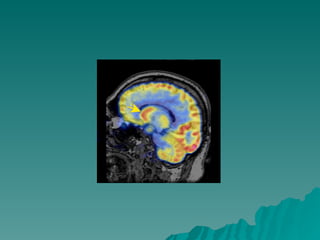

Corpo do caudado Corte Sagital

Corpo do caudado Corte Coronal